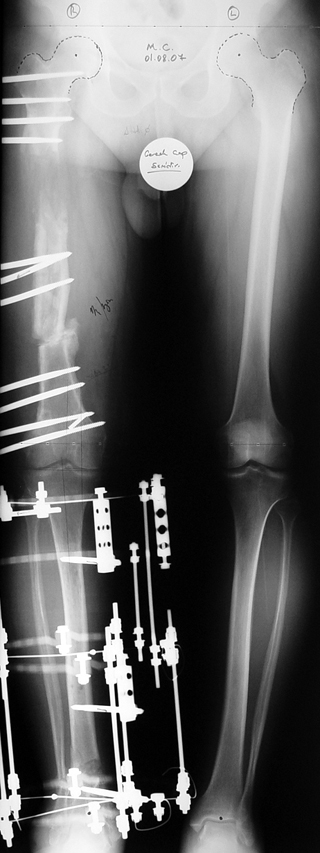

Vaka 2